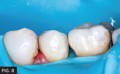

FIG. 6

BioFit matrices, Diamond wedges and TwinRing separating rings are in place.